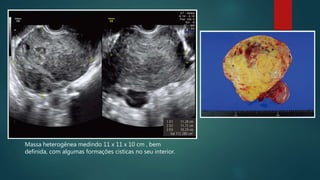

Massa heterogênea medindo 11 x 11 x 10 cm , bem

definida, com algumas formações cisticas no seu interior.